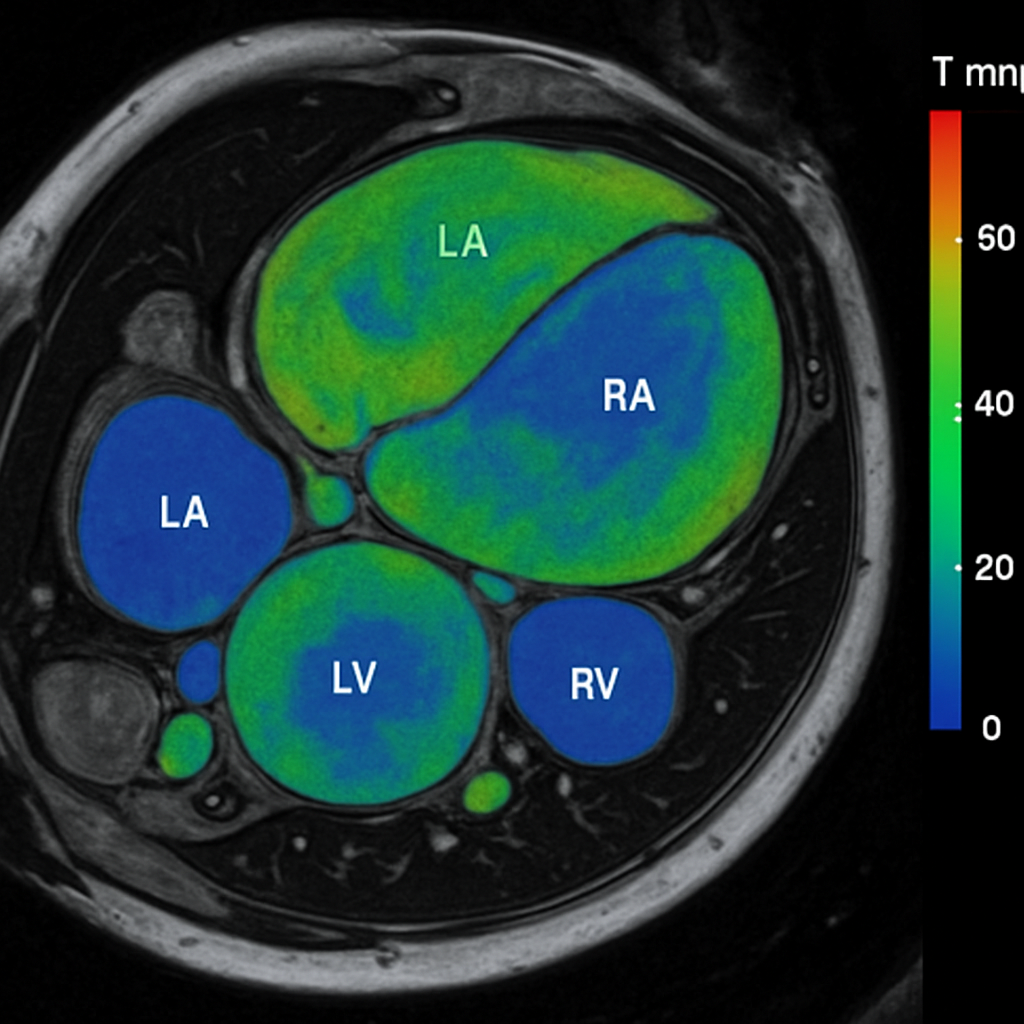

MRI — T2 Mapping (Short Axis)

T2 mapping of the heart in short-axis view with color overlay showing myocardial T2 values. Color scale. Normal myocardial T2 ~40ms at 1.5T.

MRI AI Generated 2026-03-16

T2 Mapping

T2 map, short axis, color-coded. Normal T2 ~40ms at 1.5T.